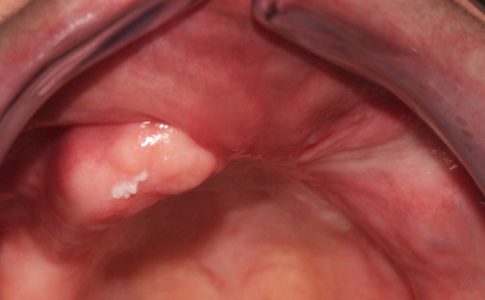

Paciente con atrofia maxilar total por MAXILECTOMÍA izquierda (para tratar un Carcinoma epidermoide)resuelta con la colocación de 4 implantes ZIGOMATICOS. La rehabilitación definitiva ha sido en metal cerámica.

Imagen de la planificación digital del caso y foto final de la paciente con la prótesis metal-cerámica.